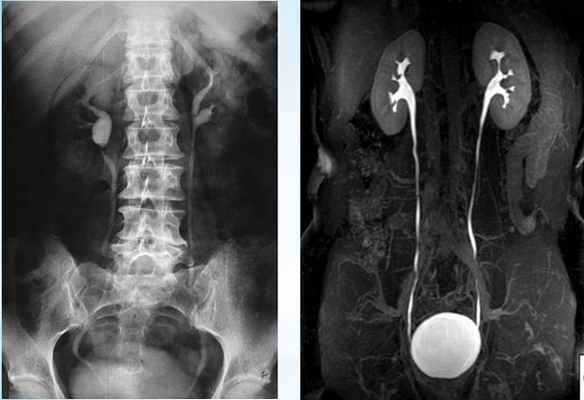

Ретроградная пиелография при стриктуре мочеточника

Рентгенконтрастная урография (экскреторная, инфузионная, ретроградная) дает возможность визуализировать ткани почек и мочевыводящие пути, определить сужение мочеточников, протяженность стриктур, оценить снижение выделительной способности почек.

Материал и методы исследования. Для решения поставленных задач, было использовано 204 пациента в возрасте от 5мес. до 82 лет, проходивших курс лечения в урологических отделениях клиник города Саранска. Контрольную группу составили 21 человек в возрасте от 17 до 25 лет, проходивших обследование в урологических отделениях по линии военкомата (допризывники) выписывающихся с диагнозом «урологически здоров». Для диагностики гидронефроза проводилась экскреторная и ретроградная пиелография. УЗИ почек, радиоизотопная ренография и рентгенологические методы исследования, в том числе обзорная урография, ретроградная уретеропиелография и ядерно-магнитная томография. С целью определения функциональной способности ночек изучалась клубочковая фильтрация, которая рассчитывалась по клиренсу эндогенного креатинина. Материал для гистологических исследований брался эксцизионно и инцизионно. Забранный материал (лоханка или часть мочеточника) фиксировался 12% растворе нейтрального формалина. Срезы мочеточника окрашивались гематоксилин эозином по Ван-Гизону. Для изучения интрамурального нервного аппарата лоханочно-мочеточникового сегмента и мочеточника материал обрабатывался по методу Бильшовского-Грос. Срезы окрашивались солями азотно-кислого серебра.